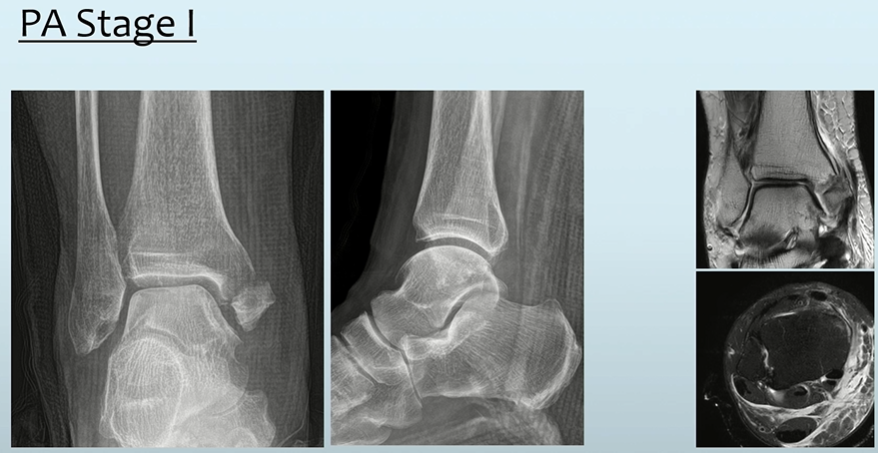

- Stage 1: MM 골절(Transverse 양상) 또는 Deltoid ligament injury

- Stage 2: PM 골절

실제 양상은 다음과 같습니다.